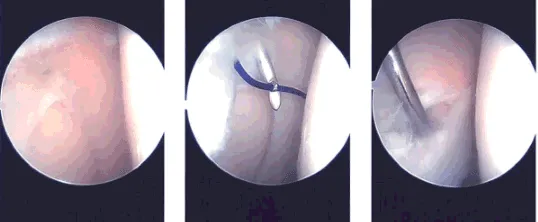

Se realizó una incisión lateral para la puerta anterior del artroscopio. El artroscopio se introdujo en la articulación patelofemoral, donde se observó sinovitis en la región suprapatelar.

Había daño condral de grado II a III en la superficie posterior de la rótula. El artroscopio se introdujo en el compartimento medial, donde no había desgarro meniscal. El cartílago estaba intacto. Había sinopolitis en el compartimento medial.

Se realizó un portal anterior medial utilizando la aguja espinal. El examen de la escotadura condral anterior mostró un LCA intacto. El examen del compartimento lateral mostró una ruptura del cuerno posterior del menisco lateral. También había sinopolitis en el compartimento lateral.

La afeitadora se utilizó para realizar la sinonovectomía tanto en el compartimento medial como en el lateral. Se afeitaba para realizar una meniscectomía del cuerno posterior del menisco lateral. También se utilizó el mordidor hacia arriba para la meniscectomía.

Ahora se introdujeron la afeitadora y el artroscopio en el compartimento patelofemoral, donde se realizó una extensa sinonovectomía del sinovio desde la bolsa suprapatelar, así como de la canaleta medial y lateral. La lesión condral de la bolsa de rótula posterior también fue desbridada con el uso de una afeitadora. Tras un riego exhaustivo se tomaron y guardaron fotos.

Imágenes intraoperatorias